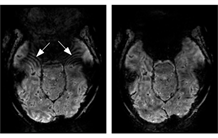

Les scanners IRM à ultra haut-champ, comme l'IRM Iseult à 11,7 T implanté à NeuroSpin, offrent des images d'une résolution exceptionnelle, mais à ces champs, divers artefacts peuvent altérer la qualité des données. Les chercheurs de l'équipe METRIC (UMR BAOBAB/Neurospin) se sont intéressés à un type particulier d'altérations :

les artefacts en forme d'ondes, causés par le déphasage intra-voxel dans les zones où le champ magnétique est inhomogène.

Pour accélérer les acquisitions, les scientifiques utilisent des techniques algorithmiques et d'échantillonnage comme GRAPPA, qui reconstruisent l'image à partir de données partiellement acquises. Les lignes de calibration (ACS), essentielles à cette reconstruction, sont souvent de basse résolution et plus sensibles aux variations locales du champ magnétique. Dans les régions où ces variations sont fortes (comme près des sinus ou du cou), le signal se déphase à l'intérieur même des voxels, créant des interférences qui se propagent et brouillent l'image finale.

- Les ACS externes (avec un temps d'écho court) réduisent significativement les artefacts, car elles préservent mieux le signal dans les zones perturbées ;